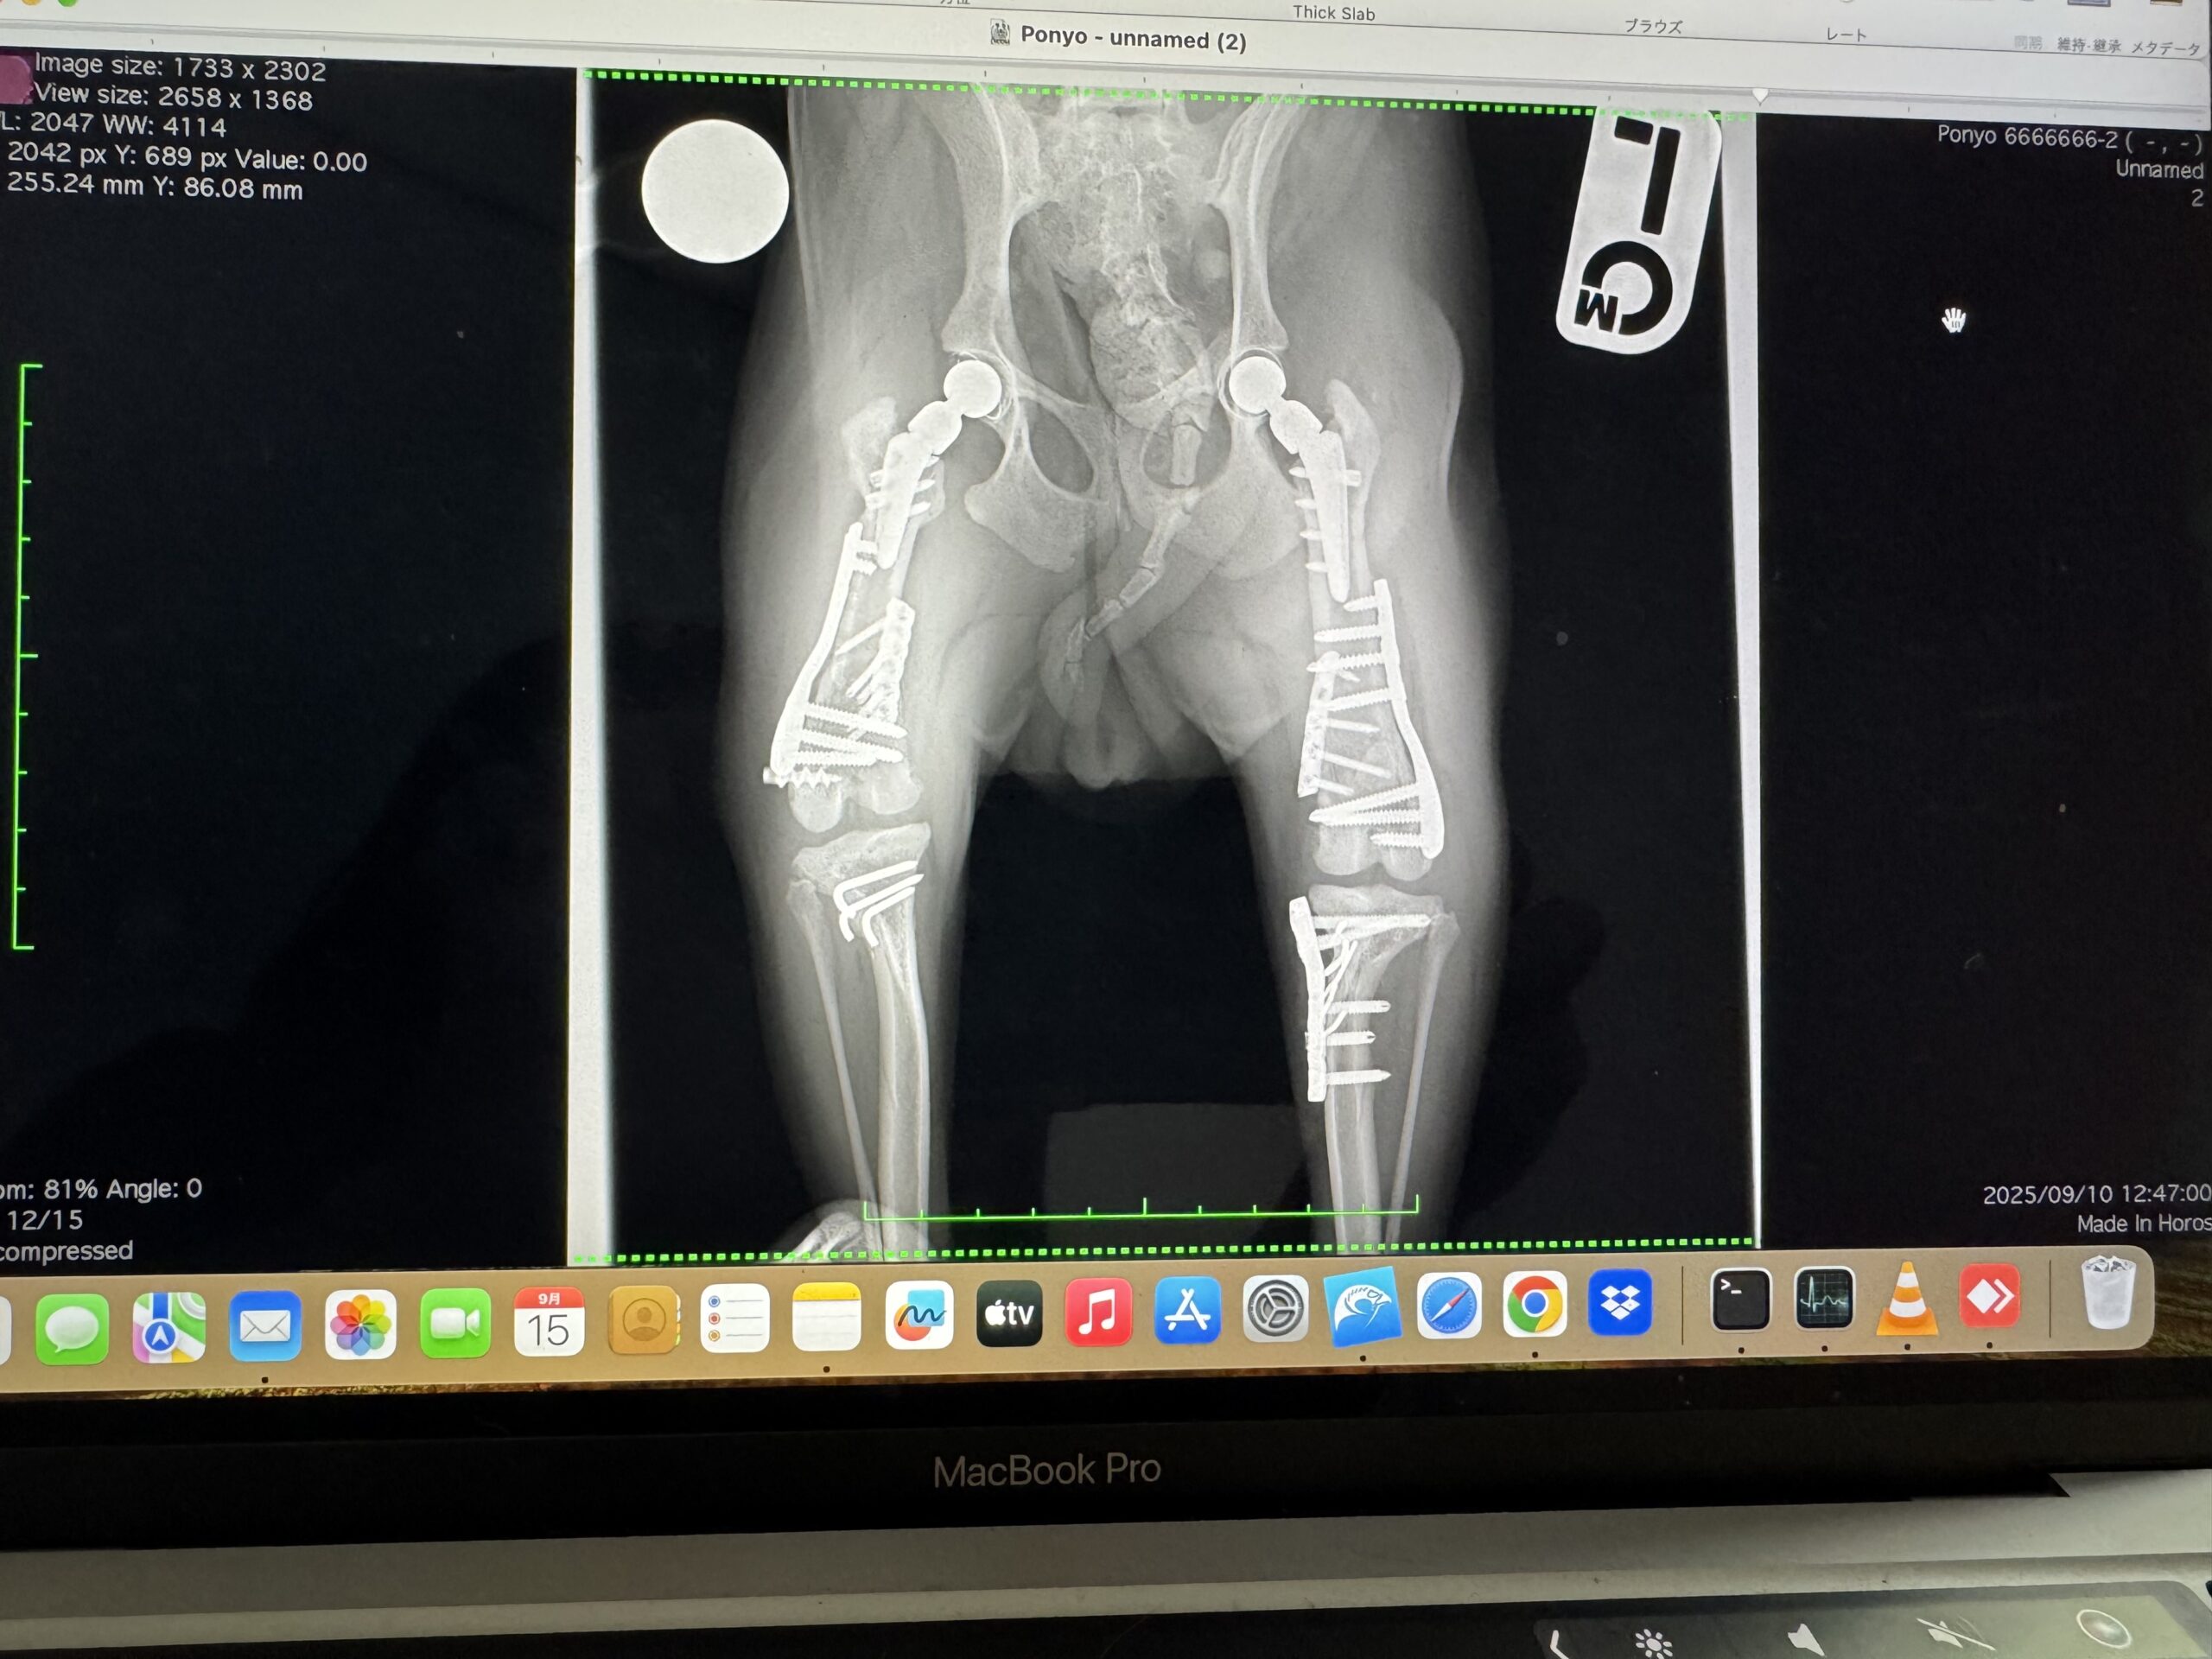

2025.9.10 右膝蓋骨外方脱臼整復再手術、左膝蓋骨内方脱臼整復再手術

レントゲンの結果、

直近で手術をした右股関節は問題なしで経過良好、左股関節も経過良好でよかったのですが…

本来安定期となり安静解除になるはずの術後3カ月になる両膝が、両方とも再脱臼との診断。

股関節の全置換術後で完全な安静生活を送っていたのに、先生も何が起こったのか分からない状況でした。

かなりの大きな衝撃を受けたとしか思えないような現象との診断ですが、ケージレストで安静にしているのでまずそんなことは起こりえません。

触診、画像などから、非常に難しい状況ではあるものの、日本ではほぼ例のない手術方法なども含めて治療方法を検討していく方向となりました。

・右膝蓋骨外方脱臼整復再手術、左膝蓋骨内方脱臼整復再手術

ただ、ぽにょの太ももの筋肉の捻る力が強いため、術後の関節に負担をかけないようアンカーのような長いボルトを入れることとなり、1か月後に20分ほどの手術で抜く方針となりました。